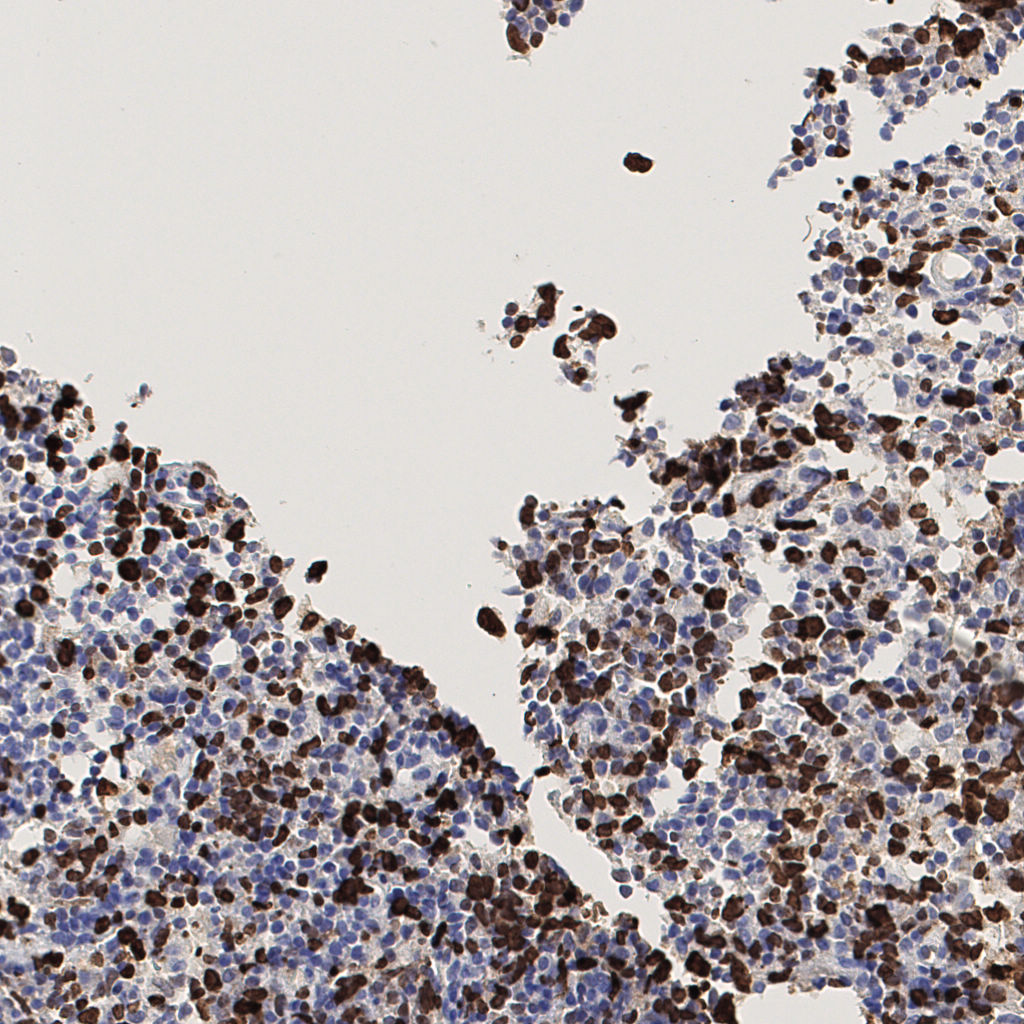

7.85%

Ki67 指数

阴 1104 阳 94

切片统计

总切片 1953

有效 288

已标记 288

有效率 15%